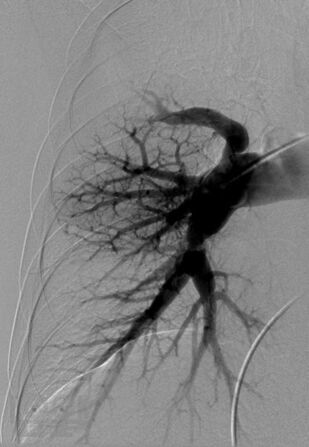

В четвертом томе четырехтомного руководства по кардиологии описываются этиология, патогенез, диагностика, клиническое течение и лечение сердечно-сосудистых заболеваний, в частности сердечной недостаточности, миокардитов, кардиомиопатий, легочной артериальной гипертензии, приобретенных пороков сердца, инфекционного эндокардита, перикардитов, опухолей и травм сердца, болезней сосудов. Приводятся также сведения об основных классах лекарственных препаратов, применяемых для лечения сердечно-сосудистых заболеваний. Руководство предназначено для кардиологов, терапевтов, врачей общей практики (семейных врачей), кардиохирургов, специалистов по рентгеноэндоваскулярной диагностике и лечению, врачей других специальностей, принимающих участие в обследовании и лечении больных с заболеваниями сердечно-сосудистой системы, и студентов высших медицинских учебных заведений.